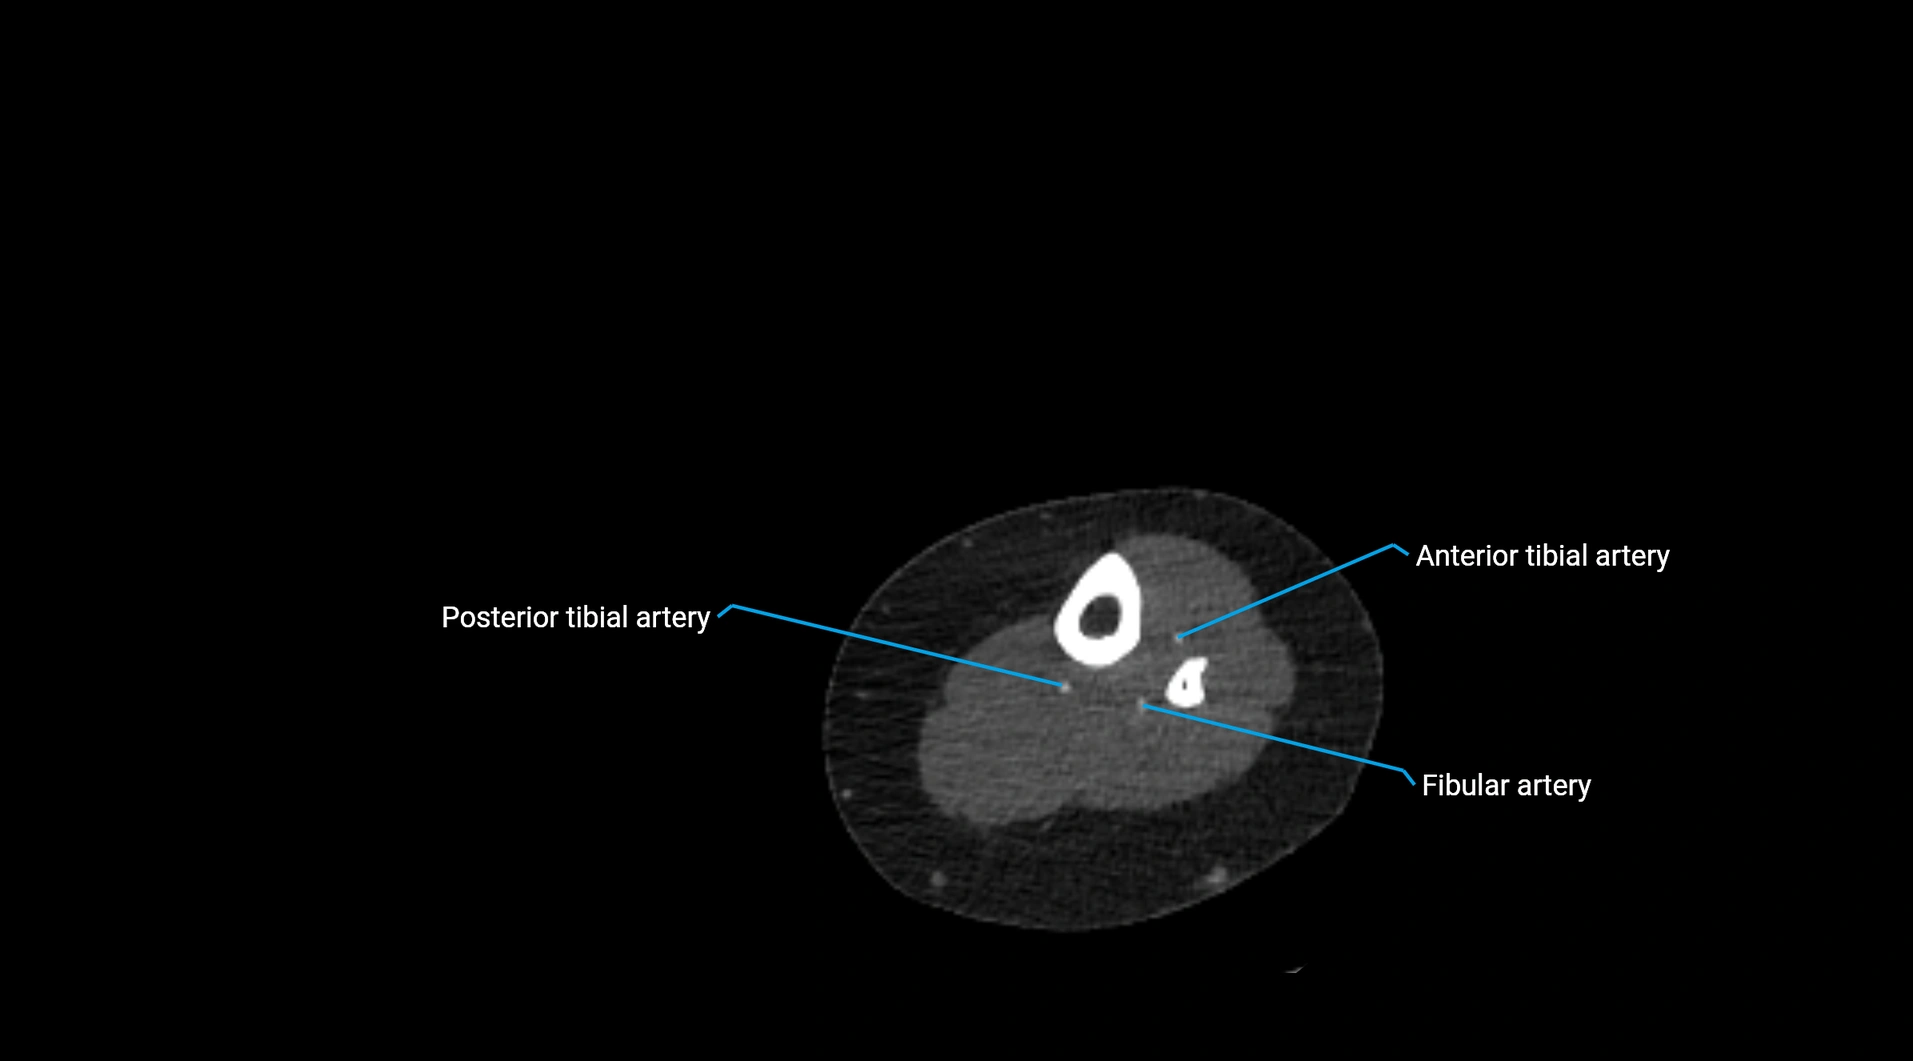

CT images

image